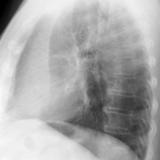

LUL Collapse Case 3 Lateral

Date: 02/19/2004

Views: 3369